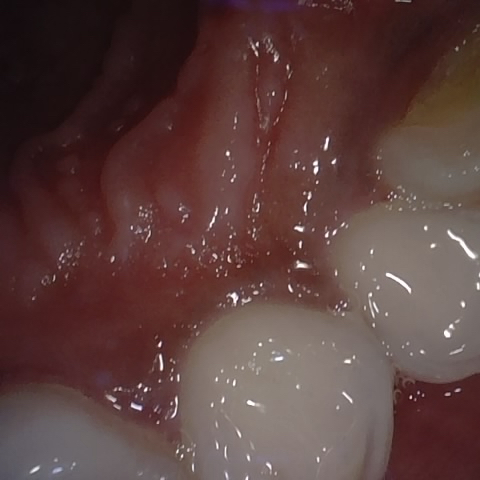

Image 678 / 1103

NHD39174

Annotated as "Good"

Original Image Rendering Image